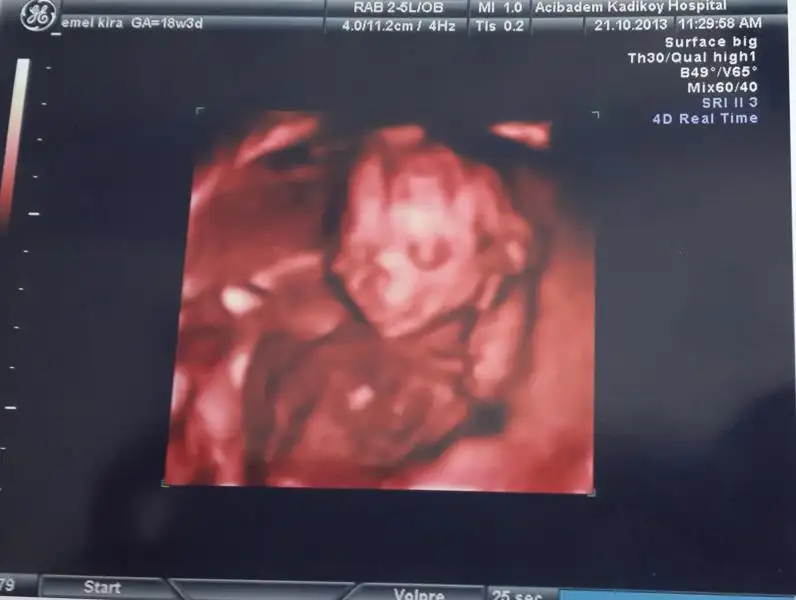

merhaba kızlar maşallah herkes alışverişe başlamış ben de az az başladım :) benim de oğluşum olacak inşallah. detaylı ultrasona da girdim kendi drum yaptı başka dr a gitmedim 24. haftada geldiğinde bidaha bakarız dedi 19+1 de gitmiştim çünkü. ama yüzü çok belirgindi çok muhteşem bir duygu. bugün de ilk defa tekmelerini net bir şekilde hissettim karnım hopladı :)